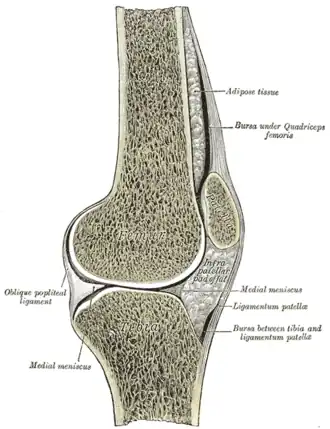

Sagittal section of right knee-joint, thus showing only frontal bursae. | |

The knee bursae are the fluid-filled sacs and synovial pockets that surround and sometimes communicate with the knee joint cavity. The bursae are thin-walled, and filled with synovial fluid. They represent the weak point of the joint, but also provide enlargements to the joint space.[1] They can be grouped into either communicating and non-communicating bursae or, after their location – frontal, lateral, or medial.

In front, there are five bursae:

- the suprapatellar bursa or recess between the anterior surface of the lower part of the femur and the deep surface of the quadriceps femoris.[2] It allows for movement of the quadriceps tendon over the distal end of the femur. In about 85% of individuals, this bursa communicates with the knee joint. A distension of this bursa is therefore generally an indication of knee effusion.[3]

- the prepatellar bursa between the patella and the skin[2] It allows movement of the skin over the underlying patella.

- the deep infrapatellar bursa between the upper part of the tibia and the patellar ligament.[2] It allows for movement of the patellar ligament over the tibia.[4]

- the subcutaneous (or superficial) infrapatellar bursa between the patellar ligament and skin.[2]

- the pretibial bursa between the tibial tuberosity and the skin.[2] It allows for movement of the skin over the tibial tuberosity.[4]